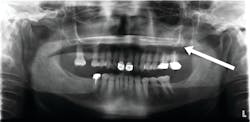

It is reported that pseudocysts are found in up to 14% of the population.2 Antral pseudocysts are formed by the inflammatory serous exudate accumulating below the sinus membrane and causing a dome- or sessile-like elevation with a faintly radiopaque and well-delineated dome appearance. Although the cause has not been definitively confirmed, antral pseudocysts have been associated with allergies, respiratory and viral infections, and forced-air heating (figure 1).2

The clinician may confuse the antral pseudocyst with a nonodontogenic cyst, an odontogenic cyst (such as a dentigerous cyst, an odontogenic keratocyst, or a residual cyst), or an inflammatory lesion (such as a radicular cyst, an odontogenic tumor, or a nonodontogenic tumor). When viewing the finding on a panoramic image, the next step is to acquire a periapical image of the area in question. The vitality of any teeth in the area should be determined, and unrestored teeth without evidence of pulpal or periodontal disease should test vital if the area in question is an antral pseudocyst of nondental origin and should allow the elimination of other entities in some cases. However, when the location or the presentation of the entity is in question, further testing is usually needed, such as advanced imaging, biopsy, or fine needle aspiration. Referral to an oral surgeon or an otolaryngologist would be appropriate.5,6